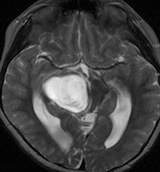

4回目のアバスチン投与後

アバスチンをどれだけ続ければいいのかははっきりしていません。2週間おきに6コースまでの投与が基本かもしれません。

この画像を見ると,放射線とテモダールの治療が有効であったのかなと思います。

注意,アバスチン投与を中断するとreboundで病変の急増悪が生じることがあります。